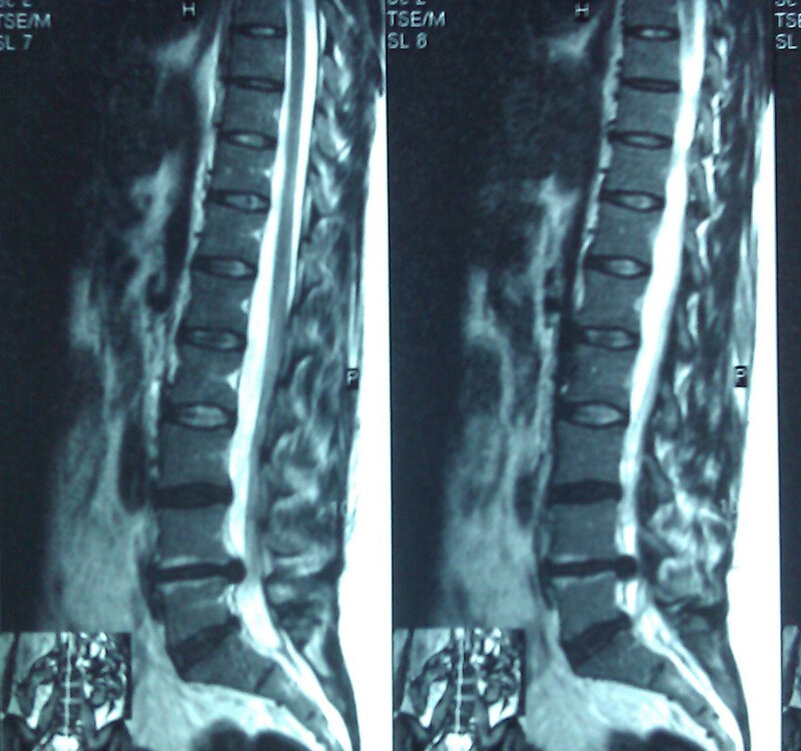

Ноющая, распирающая острая или хроническая боль — обычно обостряется при переохлаждении, нагрузке и подъеме тяжестей, какой-либо физической работе или наоборот, длительном нахождении в положении сидя, стоя или лежа. Возможные причины: миозит, межпозвонковая грыжа поясничного отдела, люмбаго, ушиб позвоночника.

Грыжа межпозвонкового диска в поясничном отделе позвоночника.

Пульсирующая, стреляющая, режущая боль — сопровождается периодически возникающей слабостью в конечностях, усиливается при ходьбе, наклонах, полностью не проходит после приема обезболивающего. Прострел может спровоцировать кашель или чихание. Таким симптомы вызывают межпозвонковая грыжа, радикулит, ишиас, остеохондроз или спондилез, травмы, растяжение или воспаление мышц.